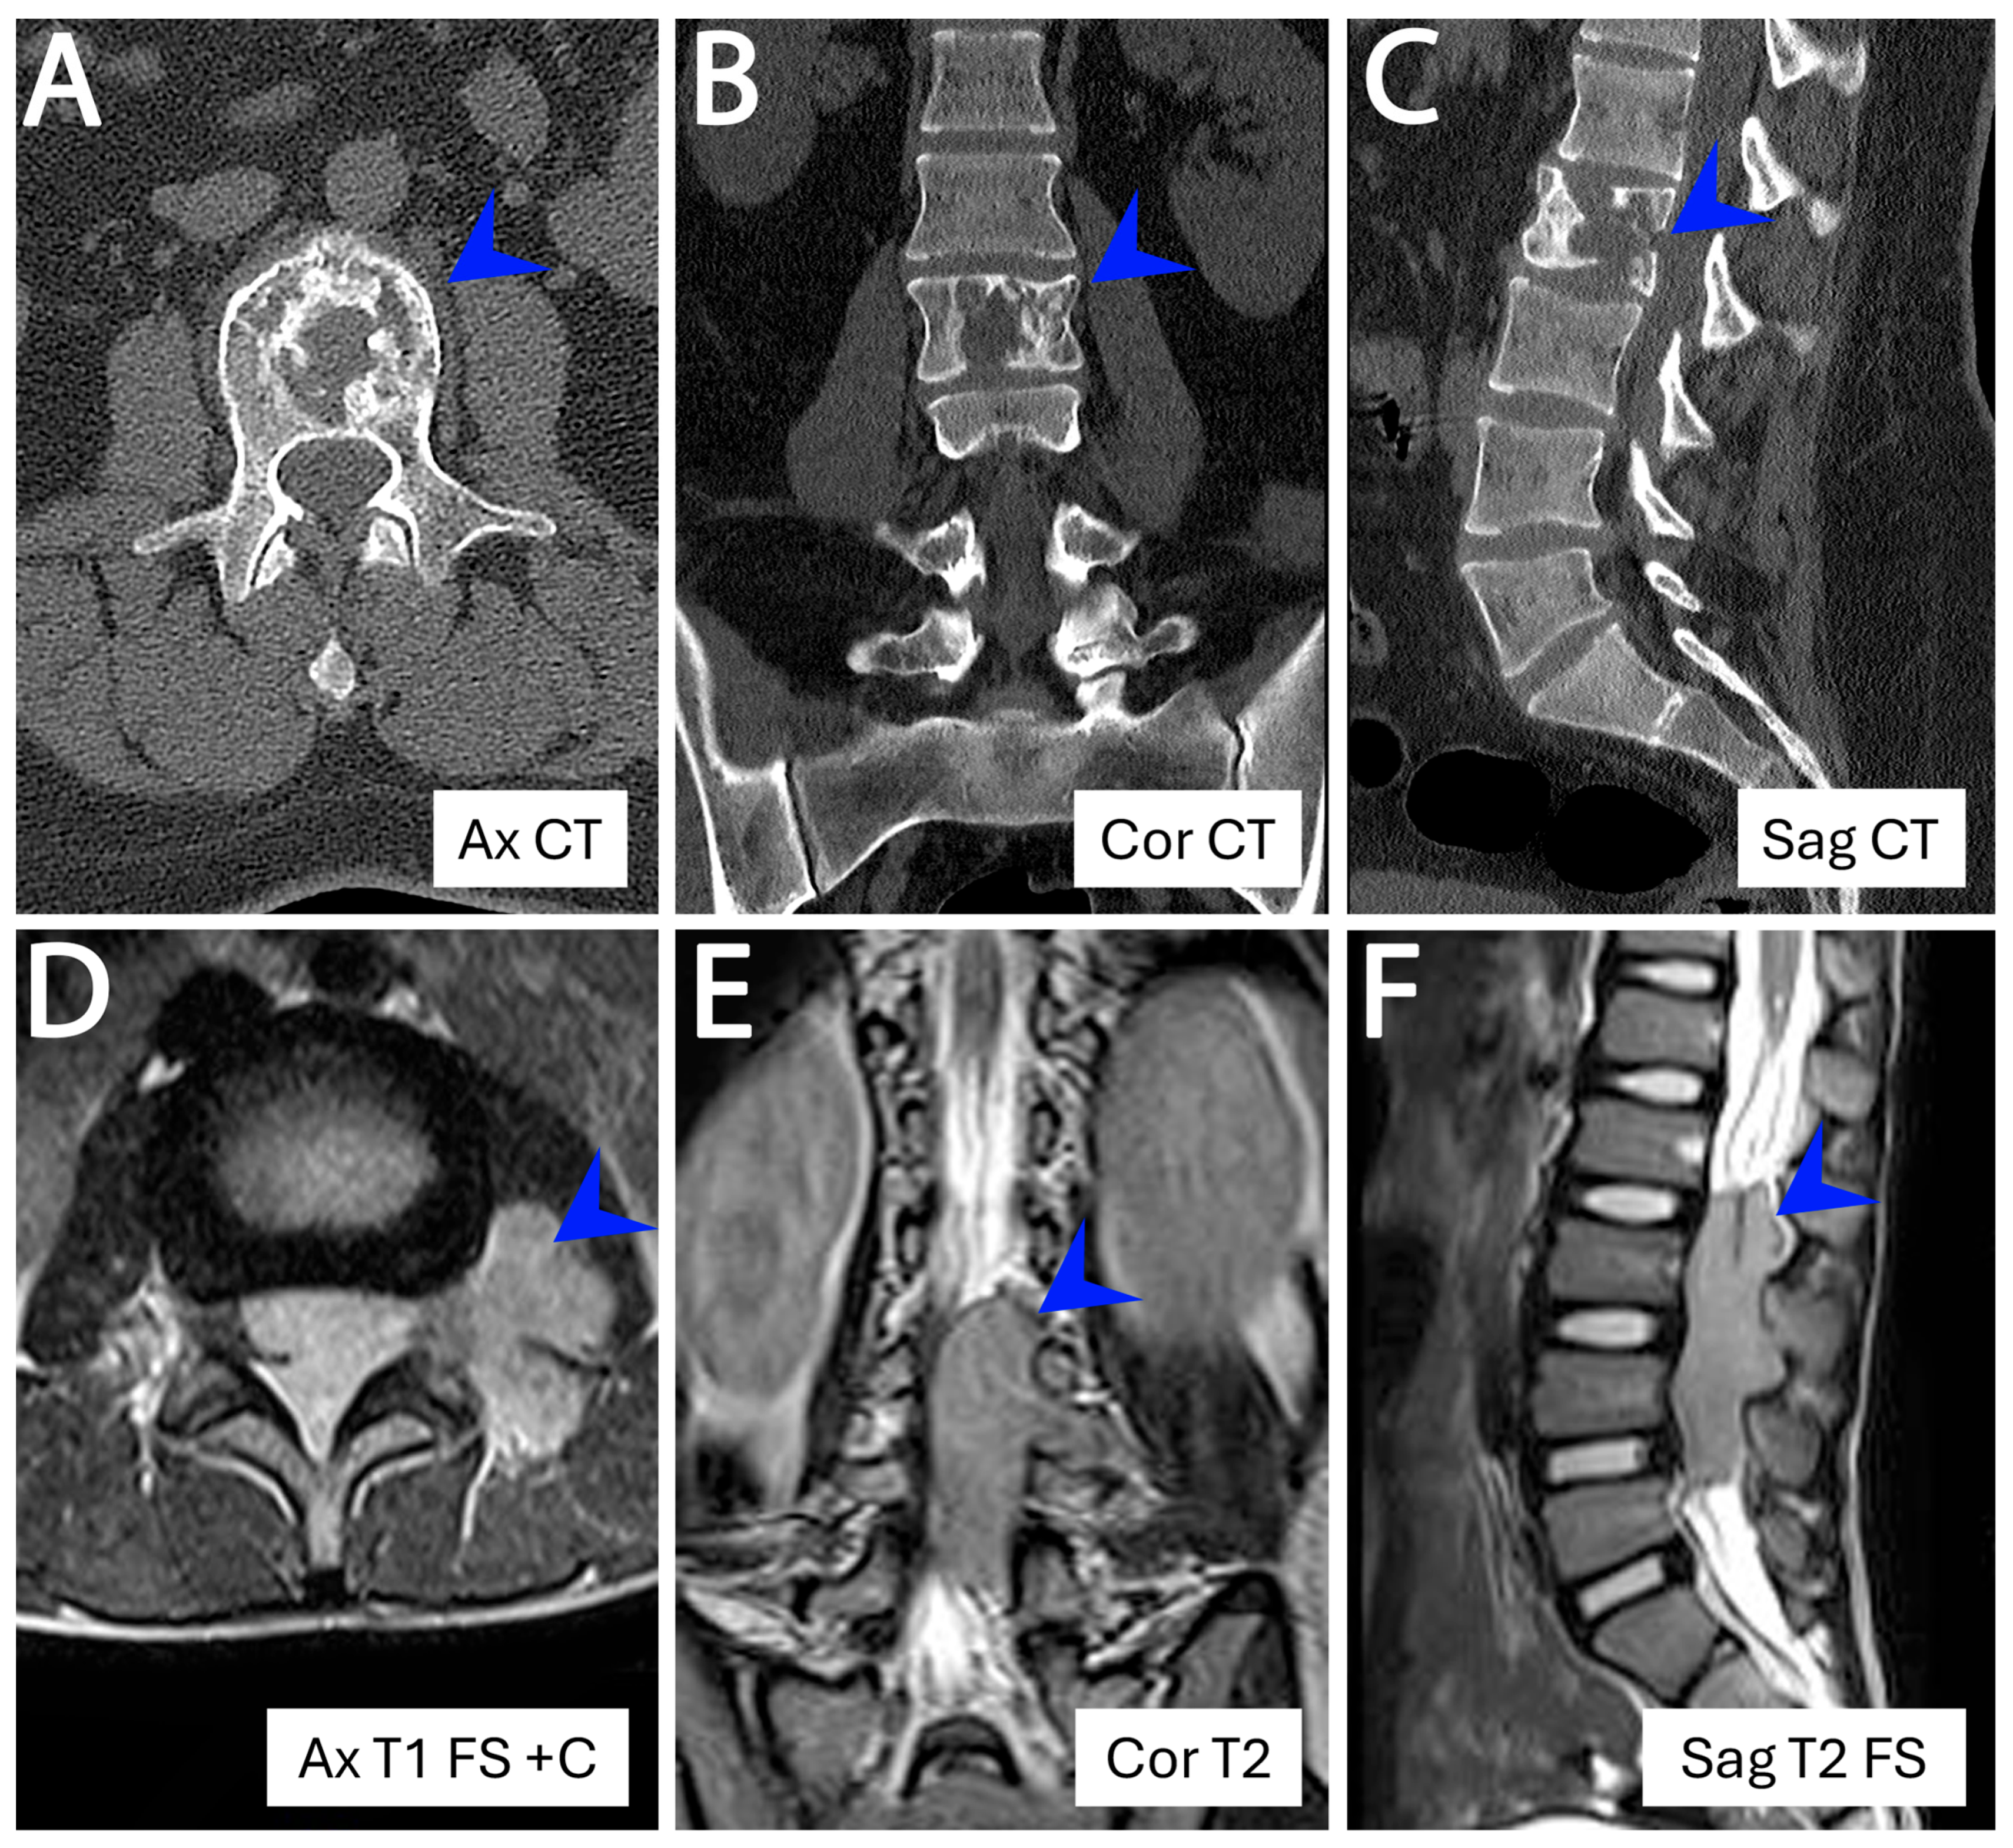

- Wright, A.; Desai, M.; Bolan, C.W.; Badawy, M.; Guccione, J.; Korivi, B.R.; Pickhardt, P.J.; Mellnick, V.M.; Lubner, M.G.; Chen, L.; et al. Extraskeletal Ewing sarcoma from head to toe: Multimodality imaging review. Radiographics 2022, 42, 1145–1160. [Google Scholar] [CrossRef]